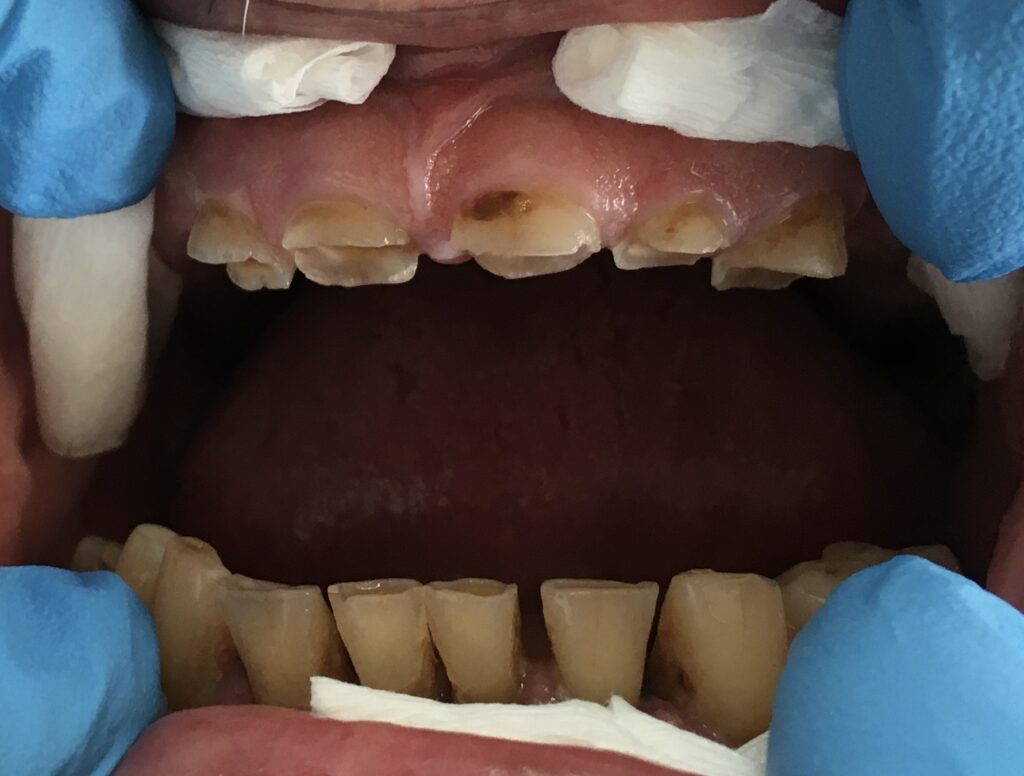

Każdy uśmiech ma swoją historię – my pomagamy ją opowiedzieć na nowo. Dzięki indywidualnie dobranym planom leczenia przywracamy pacjentom nie tylko piękny wygląd zębów, ale również komfort i funkcjonalność w codziennym życiu. Poniżej przedstawiamy wybrane przypadki metamorfoz, które pokazują, jak zaawansowana protetyka, nowoczesne techniki odbudowy oraz precyzyjne leczenie endodontyczne potrafią całkowicie odmienić uśmiech.